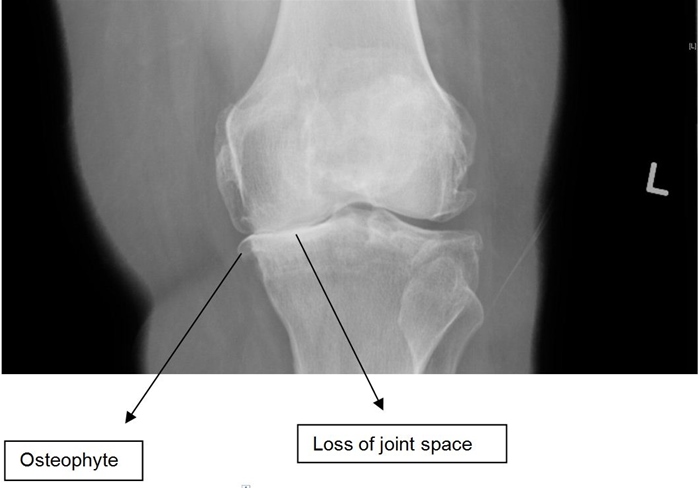

Osteoarthritis

.,

Knee x-ray findings in patients with osteoarthritis include joint space narrowing, subchondral sclerosis, osteophyte formation, and subchondral cysts.